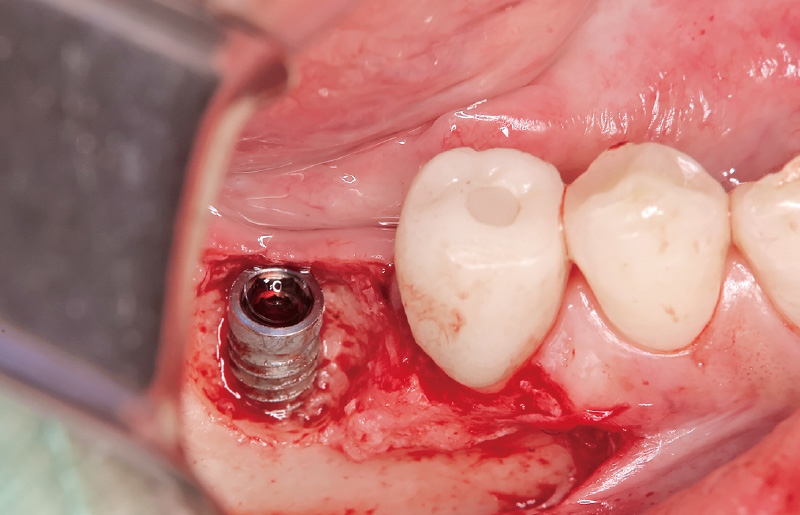

図2 全層弁剥離を行う。頰側に骨欠損を認める。 -

図3 インプラント部の感染性肉芽組織に対しては、「アドベール SH」の「不良肉芽除去」モードを使用し、インプラント体には非接触で損傷を与えることなく、また骨に熱損傷を起こすことなく、効率的に感染組織を除去した。 -